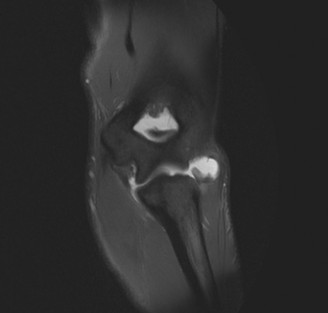

The patient undergoes conservative management consisting of rest, anti-inflammatory medications, and physical therapy. After six months, he is still not able to return to play and has progressively worsening symptoms with attempted throwing. He has a moderate elbow effusion as well as a 20-degree flexion contracture. An elbow MRI arthrogram is obtained and shown (Fig. 2–112). He elects to proceed with elbow arthroscopy. Intraoperative arthroscopic images are shown (Figs. 2–113 and 2–114).

Figure 2–112